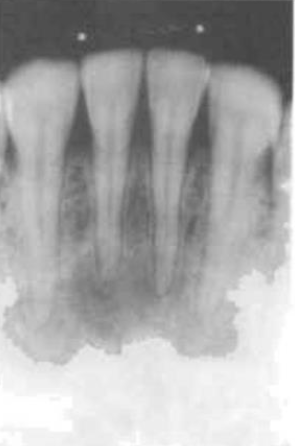

enamel & dentin

enamel → most radiopaque structure

dentin → should be uniform in density

periodontal ligament space

any definite widening in this area suggests the presence of pathology

should be narrow and even around the whole of the root surface that lies within the bone

lamina dura

is a radiographic artifact and it would be unwise to place to critical an interpretation on the variation in its appearance in diagnosis

despite the definite appearance of a white line surrounding the roots of teeth within bone, investigation has revealed that there is no increase in mineralization of the cancellous bone lining the tooth socket

pulp and pulp stones

pulp chamber & larger canals → readily visible on the radiograph